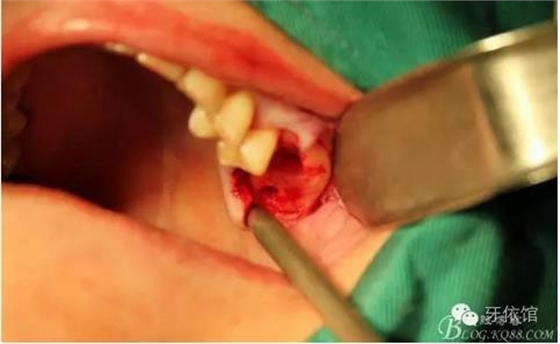

上6分根

依次拔除3個根

先在右上7的位置擴孔同時做內(nèi)提升

再在右上6牙根間隔擴孔、內(nèi)提